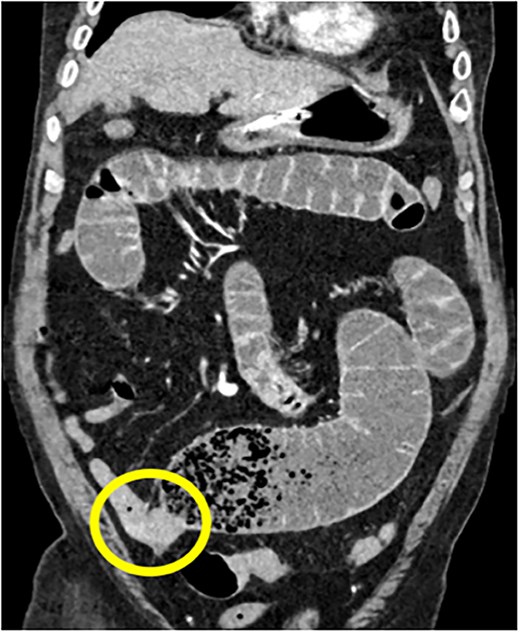

Our case series includes six patients from ages 55–88 years diagnosed with small intestinal GISTs, presenting with varied clinical manifestations between 1 January 2023 and 31 June 2024. The most common presentation was gastrointestinal bleeding in three cases (Figs 1 and 4), followed by one case each of intestinal obstruction (Fig. 3) and perforation (Fig. 5), both of which presented with abdominal pain. One patient was incidentally diagnosed (Fig. 2) during imaging for unrelated symptoms. Tumour locations included the jejunum in three cases, duodenum in two cases, and one in ileum. Tumour sizes ranged from 2 to 15 cm. Surgical interventions included segmental bowel resections with anastomosis for jejunal and ileal tumours, and wedge resections for duodenal lesions. Postoperative recovery was generally uneventful, except for two cases of paralytic ileus, which resolved with conservative management. Histopathology confirmed the diagnosis of GIST with low mitotic index of ≤5 mitoses/mm2, except for one case where wit was >5 mitoses/mm2.

75Y/M with upper abdominal pain, vomiting, abdominal distention, coronal view of the CECT abdomen showing intraluminal mass in the distal jejunum, causing dilatation of the bowel proximall.